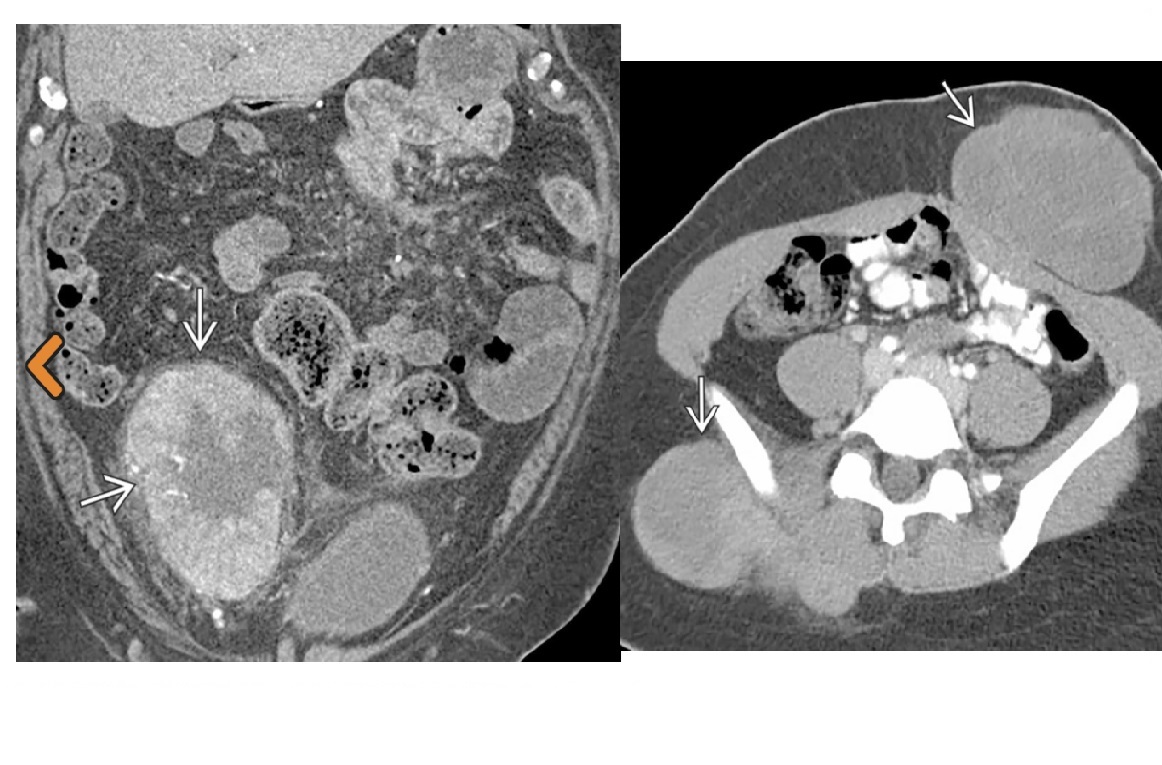

CT enterography features of active Crohn’s disease

**mucosal hyperenhancement **- most sensitive indicator but seen in other bowel diseases most specific sign for chrons - **Prominence of the vasa recta adjacent to the inflamed loop of bowel (comb sign) along with increased mesenteric fat attenuation** wall thickening (thickness >3 mm) CT enterography to depict extra-enteric disease/complications including -obstruction -sinus tract -fistula and abscess formation long-standing/inactive features include -submucosal fat deposition -pseudosacculation -surrounding fibro-fatty proliferation -fibrotic strictures MR enterography and enteroclysis - MR enteroclysis was superior to MR enterography in demonstrating mucosal abnormalities. -MR enteroclysis better bowel distension but not necessarily better diagnostics -MR enterography is more acceptable to the patient than MR enteroclysis